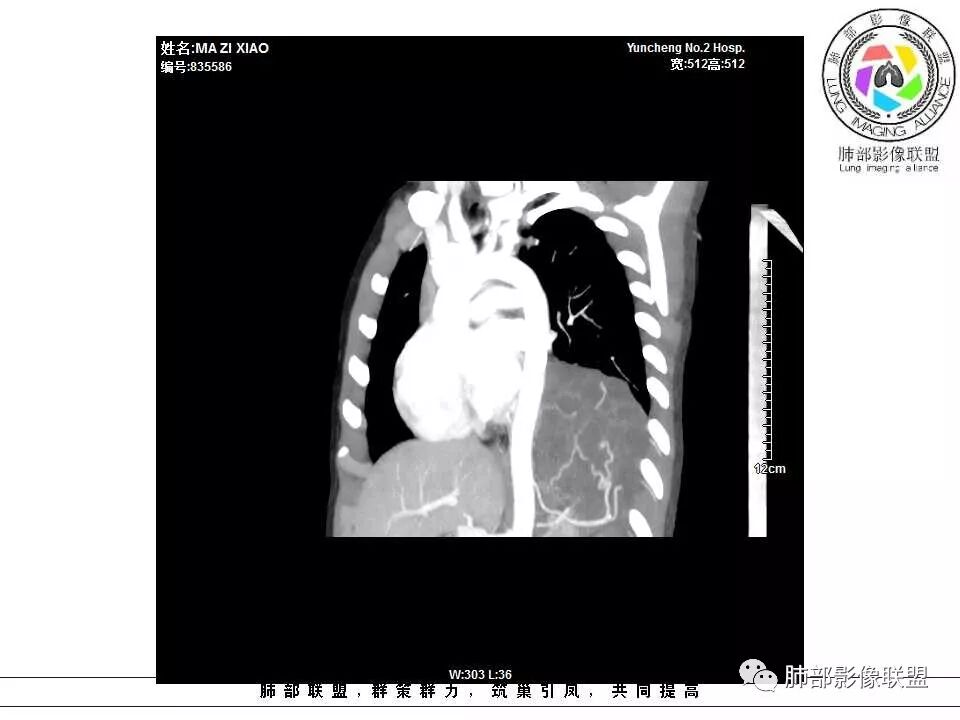

肺隔离症,供血动脉来源腹主动脉

左下肺囊性占位,多发分隔,增强分隔及边缘强化,腹主动脉供血,考虑肺隔离征。

儿童左下肺囊性占位,多发分隔,增强分隔可见强化,腹主动脉供血,肺隔离征。

左下肺囊性团块灶,多发分隔,增强分隔及边缘强化,主动脉供血,考虑肺隔离症,叶外型。

左肺下叶囊性变,可见多发分隔,增强后分隔及边缘可见强化,并可见降主动脉分支进入,考虑叶外型肺隔离症

电话随访,患者在西安某医院手术,为肺隔离症,供血两支动脉,均来自腹主动脉,引流入肺静脉。